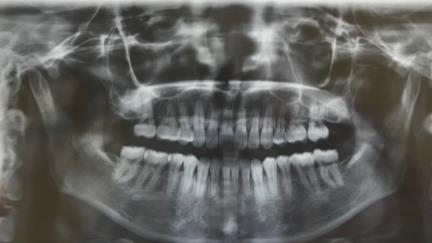

不過,智齒牽引本身並不簡單,尤其是成年人,牙齒骨質發育基本完成了,再對智齒進行牽引,難度大,過程複雜,需要的時間比較長,所以不少**可能並不適合做支持牽引,反而更適合種牙。

因此,到底是該做智齒牽引,還是該種牙,哪種結果更好一些?這個(ge) 是沒有一個(ge) 具體(ti) 說法的,需要醫生根據大家的智齒情況綜合評估後才能得出初步結論。無論如何,找正規機構和專(zhuan) 業(ye) 醫生就診,醫生會(hui) 給你合理的診療建議。